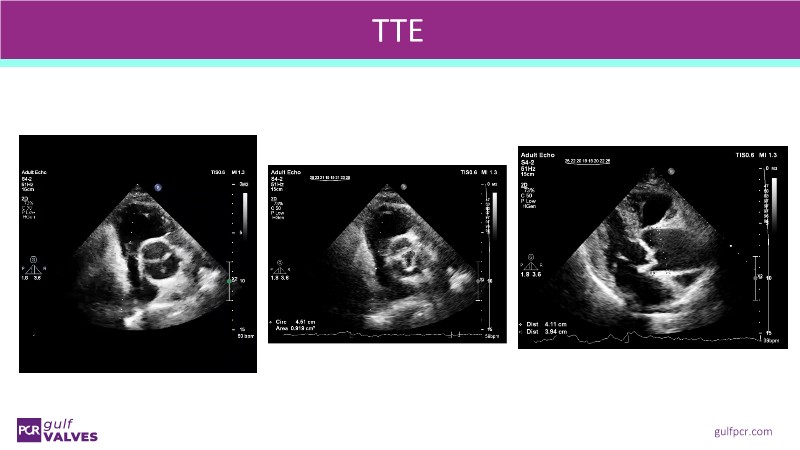

Join this comprehensive session to explore the Myval transcatheter heart valve series, featuring the latest clinical updates from two large randomized controlled trials—Landmark and Compare TAVI. Learn from real-world experiences, including recorded cases, and understand how these innovations translate to complex patient demographics in daily TAVI practice.